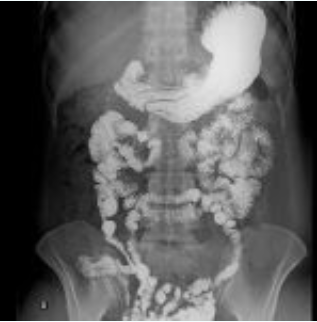

Figura 1: Exame de trânsito intestinal mostrando peristalse e preenchimento do intestino delgado com bário. Fonte: Radiopaedia

O exame de trânsito intestinal do intestino delgado (TID), também conhecido como small bowel follow-through (SBFT), é um estudo radiológico contrastado essencial para avaliar a anatomia, motilidade e integridade da mucosa do intestino delgado. É indicado em casos de suspeita de doença inflamatória intestinal, obstrução, má absorção e dismotilidade.

O contraste mais utilizado é o sulfato de bário, devido à sua baixa absorção sistêmica e excelente aderência mucosa. Em casos de suspeita de perfuração, utiliza-se contraste iodado hidrossolúvel.